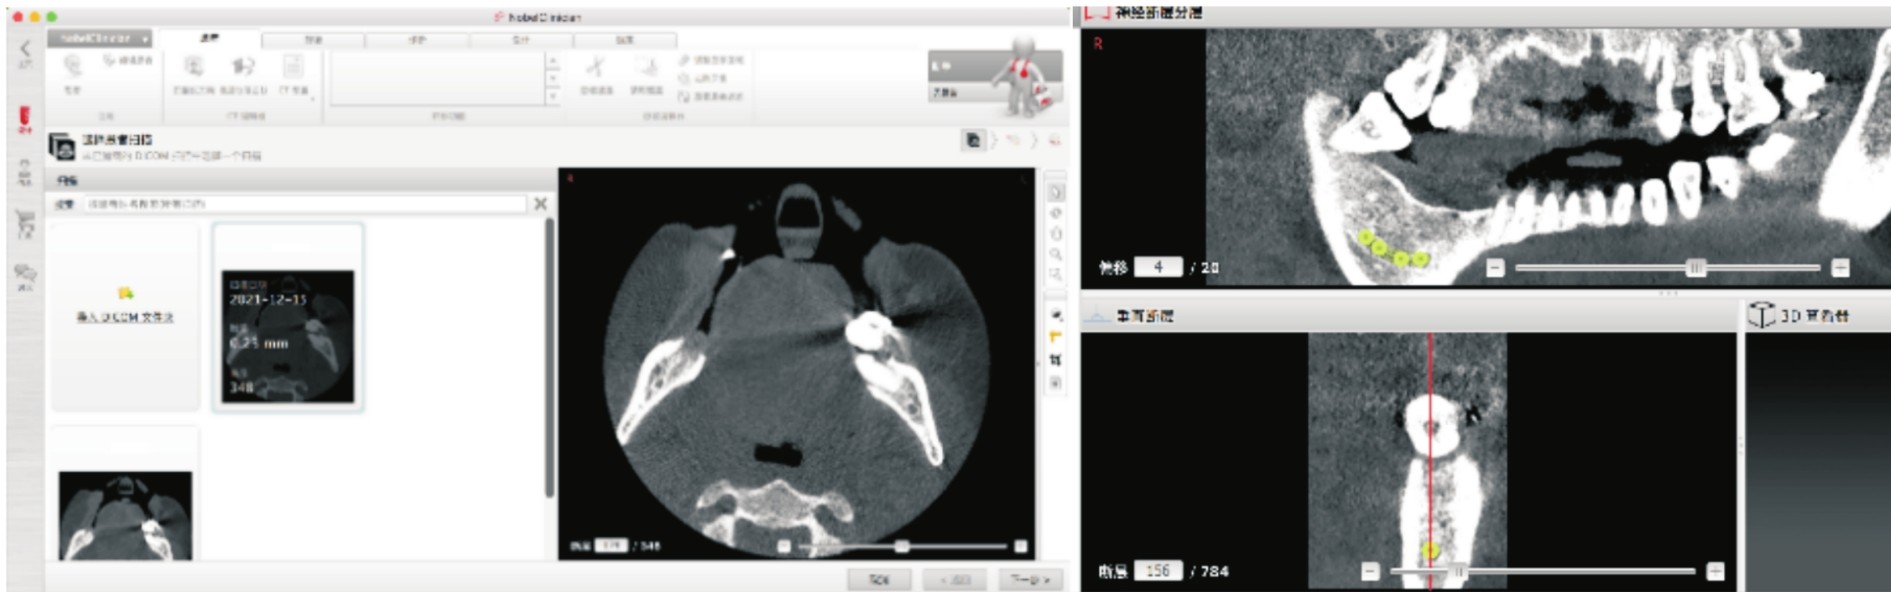

通过CBCT数字化影像,医生可充分了解种植术区可用骨量、牙槽骨密度、牙根走向、邻近重要解剖结构等信息(见图4-2)。

图4-2 CBCT图像